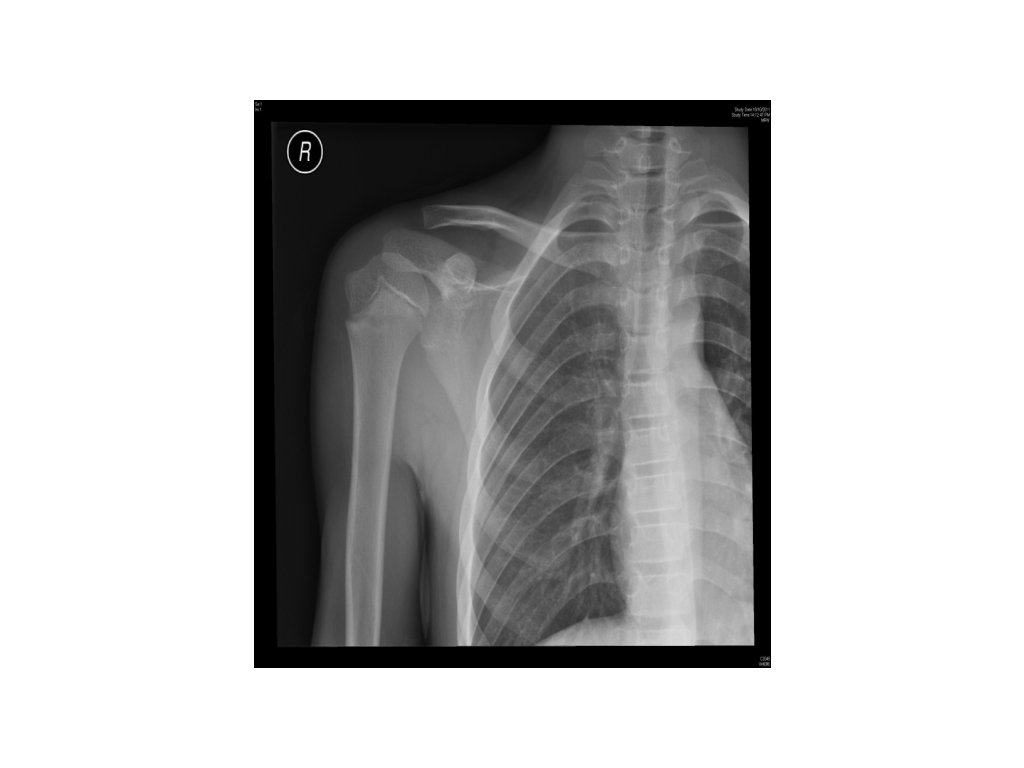

Case 1 • 11/M • Fought with classmate • Right arm pain with tenderness

1. What is the X-ray finding? • Rediolucent transverse line at neck of right humerus 2. Name three differential diagnoses from the X -ray finding. 3. What will be your management?

1. What is the X-ray finding? • Rediolucent transverse line at neck of right humerus 2. Name three differential diagnoses from the X-ray finding. • Normal variant of epiphyseal line • Little League’s syndrome (overuse syndrome) • Post-traumatic fracture of NOH 3. What will be your management?

1. What is the X-ray finding? • 2. Rediolucent transverse line at neck of right humerus Name three differential diagnoses from the X-ray finding. • Normal variant of epiphyseal line • Little League’s syndrome (overuse syndrome) • Post-traumatic fracture of NOH 3. What will be your management? • Immobilization (arm sling) and FU